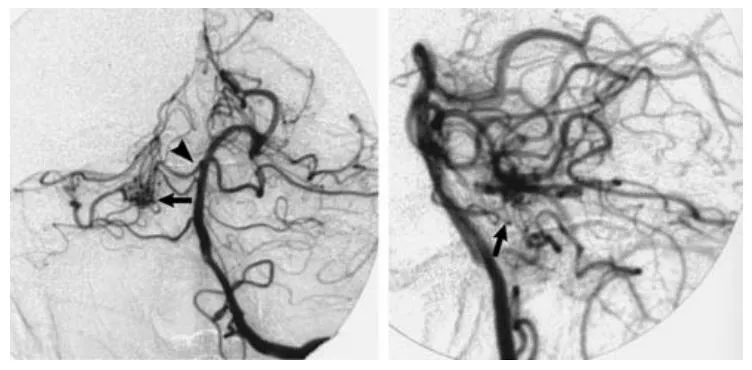

进一步的血管造影检查明确:在脑干右侧区域存在一个动静脉畸形的畸形血管巢,该血管巢由双支小脑上动脉共同供血(图2)。

图2 左侧椎动脉数字减影血管造影正位(左图)与侧位(右图)像(动脉期),清晰显示畸形血管团(箭头指示)由双支小脑上动脉(箭头端指示)供血